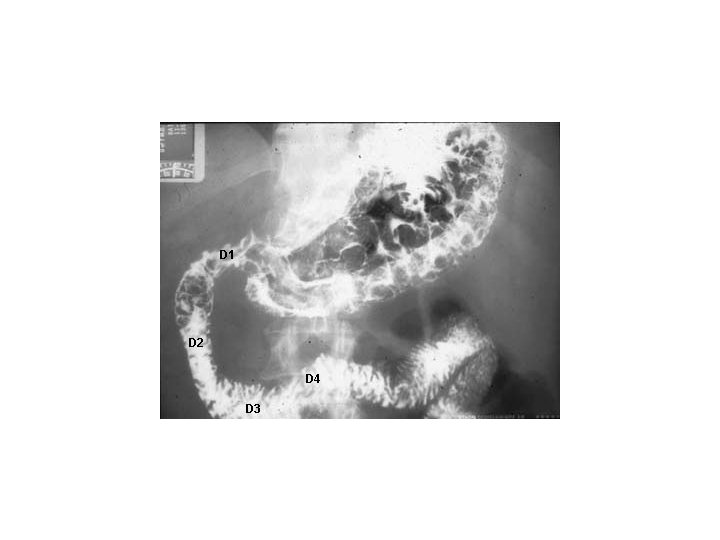

ANATOMIE DESCRIPTIVE : • I. Le duodénum : • Entouré sur lui- même, il décrit une boucle plus ou moins fermée : le cadre duodénal. • On distingue topographiquement 4 portions :

A. Le premier duodénum • Le premier duodénum ou partie supérieur fait suite au pylore au niveau du flanc latéral droit de la première vertèbre lombaire. • Très court, il est légèrement ascendant et à droite. • Sa portion initiale post-pylorique est mobile; elle présente un élargissement juste après le pylore : le bulbe duodénal (ulcère).

B. Le deuxième duodénum • Le deuxième duodénum ou partie descendante fait, avec la portion précédente un angle de moins de 90° (genu supérius). Il descend verticalement le long du rachis à hauteur des 4 premières vertèbres lombaires. • C'est à son niveau que s'abouchent les conduits pancréatiques et hépatique (canal ou conduit cholédoque).

C. Le troisième duodénum • Le troisième duodénum ou partie horizontale ou inférieure fait avec la portion précédente un angle de 90° (genu inferius). Il s'allonge transversalement au devant du relief vertébral et des gros vaisseaux qui forme une sorte de billot qui explique les possibilités d'écrasement de ce troisième duodénum dans un traumatisme abdominal (risque de rupture ou surtout d'hématome de la paroi entraînant un syndrome occlusif).

D. Le quatrième duodénum • Le quatrième duodénum ou partie ascendante est vertical en cranial de L 4 à L 2 sur le flanc gauche du rachis, puis se poursuit par un angle très aigu avec le jéjunum (angle duodéno-jéjunal), qui est attaché au pilier gauche du diaphragme par le muscle suspenseur du duodénum. • La longueur moyenne du duodénum est de 30 cm. Son calibre est irrégulier.